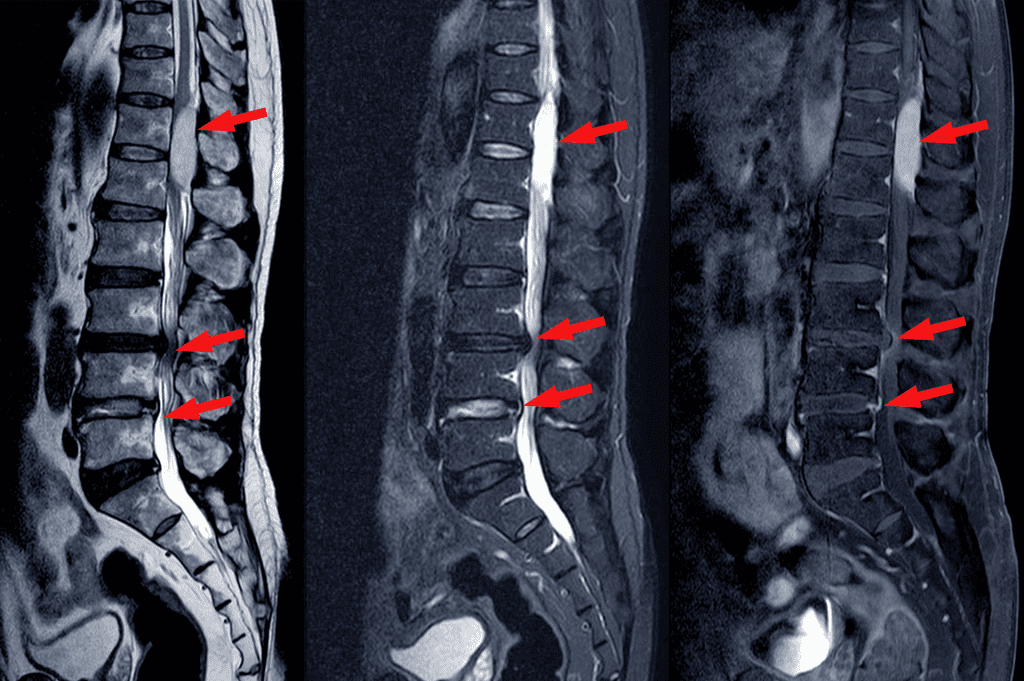

Spinal Stenosis

Compression of the spinal canal can create discomfort, numbness, and weakness. We focus on postural retraining, core stability, and mobility work to help relieve pressure and restore your ability to move comfortably.